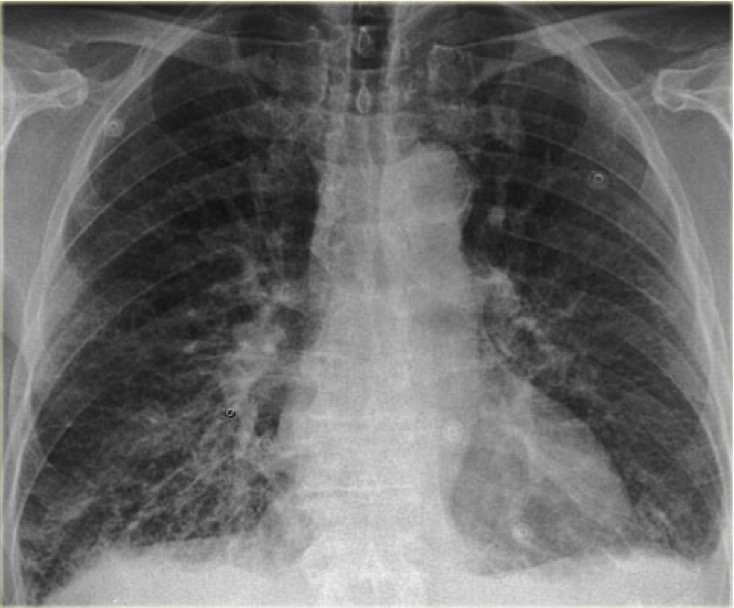

CASO: sospecha de neumonía.

Hallazgos:

- En un principio podríamos decir que existe un aumento de densidad retrocardiaco que podría ser compatible con condensación neumónica a dicho nivel, sin embargo estamos ante una placa poco inspirada, lo cual puede llevarnos a cometer errores diagnósticos.

- Se recomendó volver a realizar la radiografía, observar a continuación:

Ya no se observa el aumento de densidad retrocardiaco, la placa es normal.

INSPIRACIÓN: Una placa bien inspirada es aquella en la que se observar 6-7 arcos costales anteriores o 10-11 arcos costales posteriores. Lo contrario puede producir imágenes falsas de condensaciones o de seudocardiomegalia.